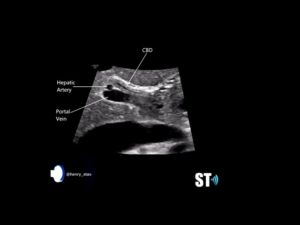

Some tips for the cbd.